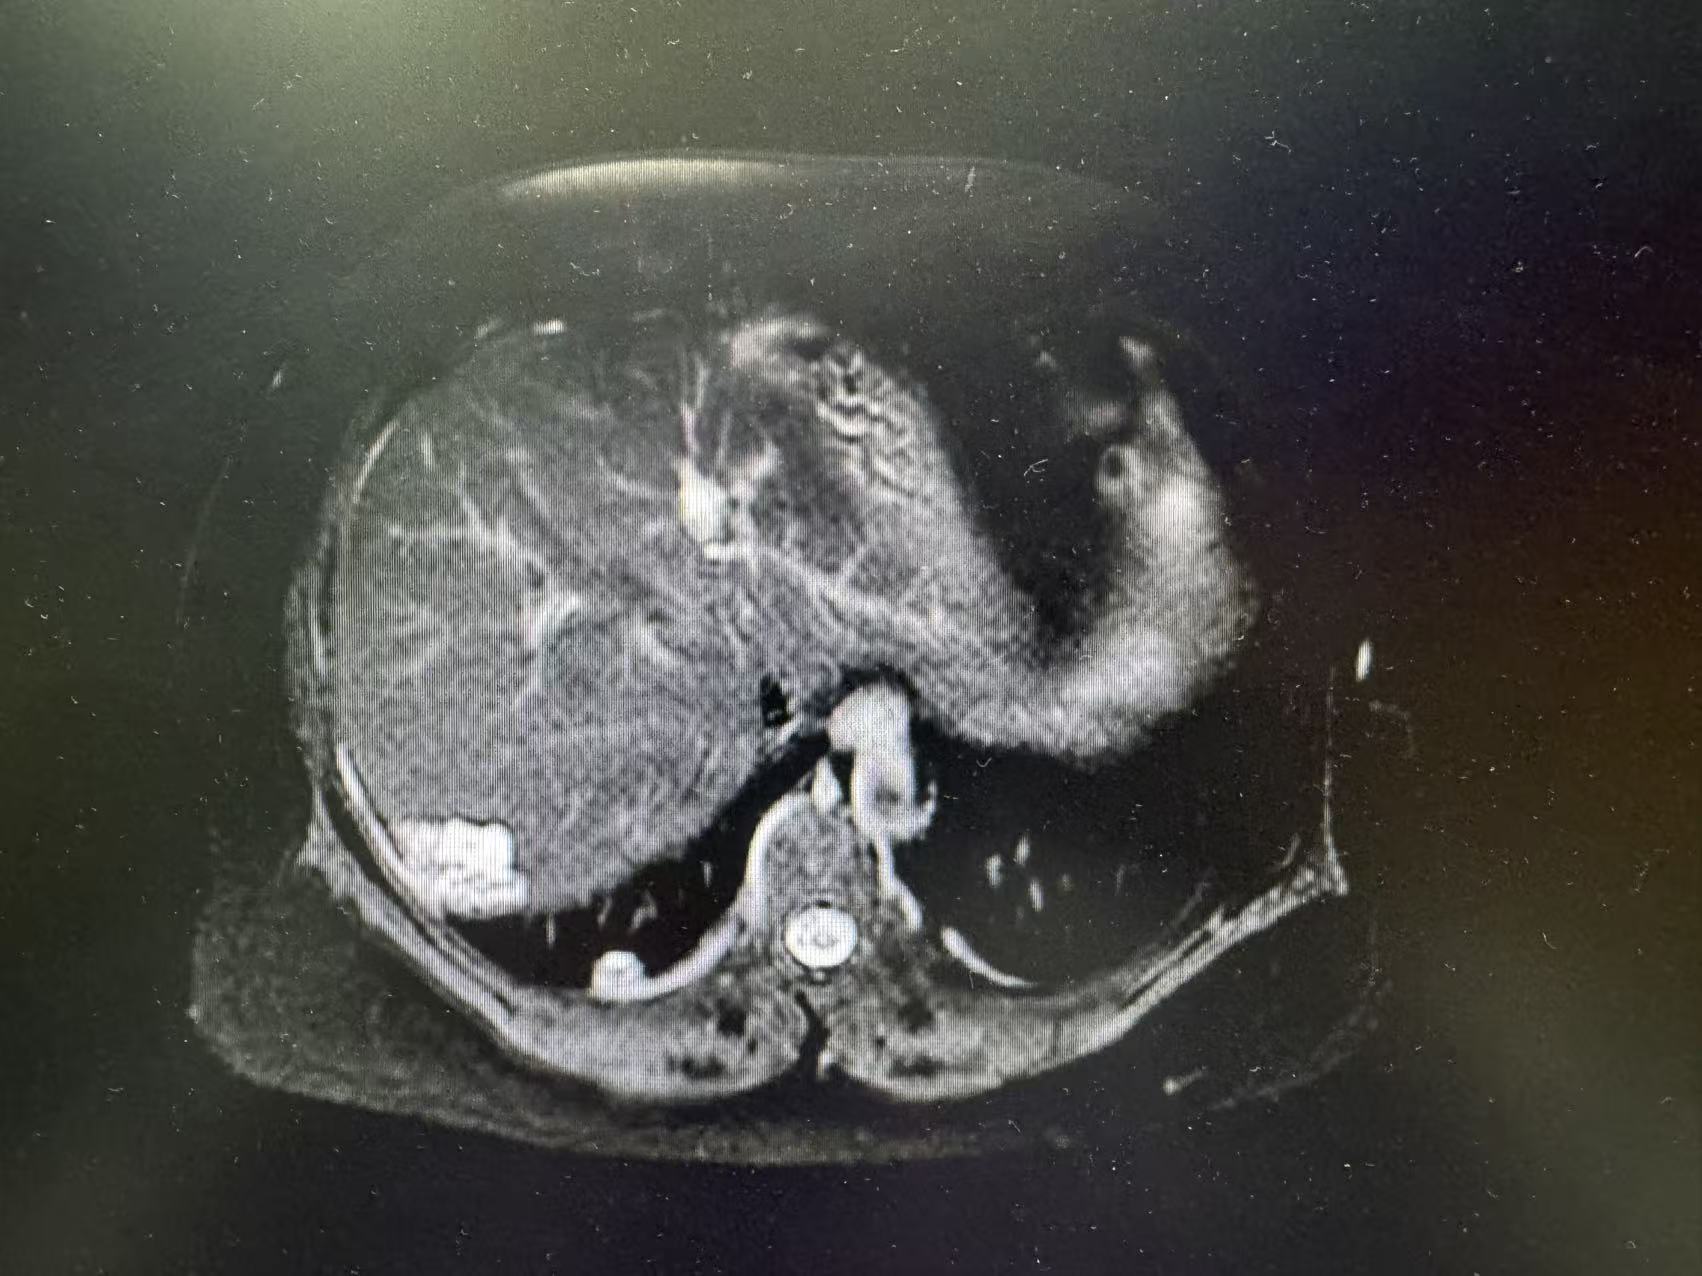

术前肿瘤影像数据

入院后,张玉宝教授立即带领团队对患者病情进行全面细致评估,启动多学科会诊(MDT),联合影像中心、麻醉科、重症医学科等专家,精准研判肿瘤侵犯范围、血管受累程度及脏器功能状态。结合二次开腹手术的特殊性,团队反复优化手术入路与切除策略,充分预判术中可能出现的致命风险,制定周密的个体化手术方案与应急预案,为手术安全筑牢坚实基础。